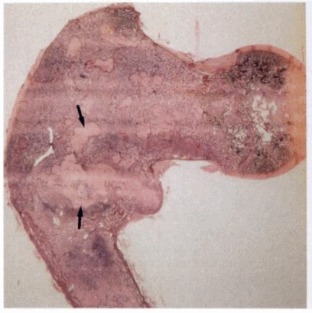

a-d Фиброзная дисплазия. Женщина 48 лет с фиброзной дисплазией, поражающей дистальный отдел плечевой кости: a) На рентгенограмме диафиза плечевой кости определяется кистозное географическое поражение с пузырным расширением. Типичное изображение в виде «битого стекла»;

b) Аксиальная Т1- взвешенная последовательность. Гипоинтенсивное поражение с истончением кортикального слоя.

c) Т2-взвешенная последовательность. Гипоинтенсивный сигнал по отношению к нормальной жировой ткани костного мозга;

d) Т1-взвешенная последовательность после введения гадолиния. Гомогенное на¬копление контрастного вещества в области поражения.